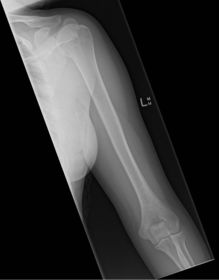

| Lateral Humerus | over rotation places the humeral head within the field of the chest |

| Lateral Humerus | epicondyles are not perpendicular humerus is internally rotated (lesser tubercle is in profile medially) overrotation |

| Lateral Humerus | ANATOMY: entire humerus: shoulder -> elbow CRITERIA: lesser tubercle in profile - arm internally rotated epicondyles superimposed POSITIONING: pt rotated 15-20 degrees from PA to get arm lateral and away from chest - flex elbow 90 degrees CR perpendicular @ midhumerus |